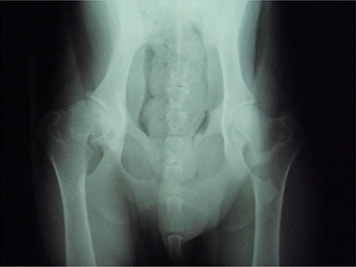

ボール遊びの後の後肢の跛行を主訴に来院されました。院内ではモンローウォーク(腰を振って歩く歩様)が認められました。レントゲン検査において、左右股関節の形成不全および比較的重度の関節炎所見を認めました。左右ともに長期に及ぶ骨関節炎の進行により、寛骨臼に重度の骨変形・骨硬化が認められました。このような症例においては、THRのカップの定着が悪くTHRの手術の成功率が下がるため、機能回復の面では劣りますが、症状がより重く、筋肉の萎縮の認められた右後肢の大腿骨頭・骨頚切除術を実施しました。関節面に関節軟骨の欠損、骨増殖体を認めました。今後は、リハビリテーションを行い、患肢の機能回復に努め、反対側の大腿骨頭・骨頚切除術を検討していく予定です。

股関節形成不全は成長期に発症する進行性の関節疾患です。中齢期以前のTHRの実施が機能回復において最も優れています。好発犬種の大型犬は成長期からの定期的な股関節のレントゲン検査をお勧めいたします。(詳しくは上記の診断を参照してください。)

術前レントゲン

術後レントゲン